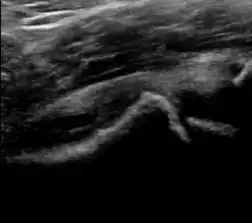

Ultrasound

Ultrasound is the first-choice technique for diagnosis of newborns hip dysplasia. In experienced hands with appropriate technology, ultrasound can also be useful during the first year of life. Some European healthcare systems encourage universal ultrasound screening in neonates between the sixth and eighth weeks. Although it shows higher initial costs caused, it leads to significant reduction in the total number and overall costs of dysplastic hips undergoing operative and nonoperative treatment.[1]

Ultrasound allows categorizing pediatric hips, according to Graf’s criteria, in four main types: normal, immature, and dysplastic (subluxed and dislocated). This classification is based on measurements of the acetabular inclination angle (alpha), cartilage roof angle (beta), and infant age. The femoral head coverage can also be determined by dividing the length of the femoral head covered by the acetabular fossa and the diameter of the femoral head. Its lower normal limits are 47% for boys and 44% for girls (Figure 11).[1]

During childhood, ultrasound is a quick method to assess hip pain and quite often may be used to avoid use of irradiating techniques, such as radiography or CT. Ultrasound allows evaluation of joint effusion, synovial thickening and neovascularity, the bone/cartilage contour, and the femoral head-neck alignment. Although sonography is extremely sensitive in detecting increased synovial fluid, it is nonspecific and cannot be used with accuracy to determine the type of fluid. Transient synovitis of the hip, despite being the most frequent cause of pain in children between 3 and 10 years, remains a diagnosis of exclusion. It usually shows anechoic fluid, but echogenic fluid can also be found. The effusion is considered pathologic when it is measured at >2 mm in thickness. The differential diagnosis is wide, including osteomyelitis, septic arthritis, primary or metastatic lesions, LCPD, and SCFE. Discrimination from septic arthritis is challenging, often requiring joint aspiration. In septic arthritis, US is able to demonstrate a hip joint effusion, synovial thickening, and cartilage damage, although the appearances are nonspecific.[1]